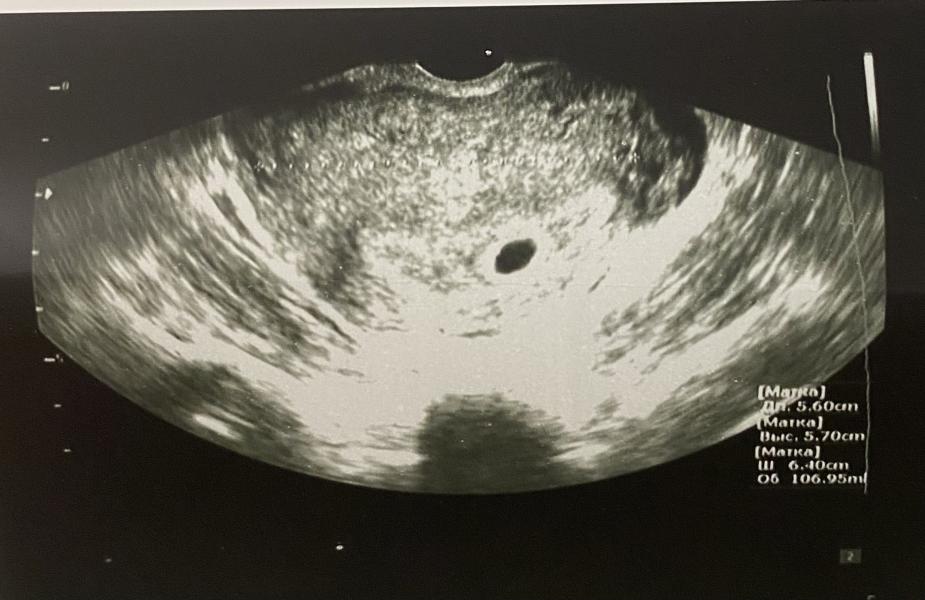

История одной фолликулярной кисты

Планировать беременность мы с мужем начали с декабря 21го года. Я подошла к этому ответственно и сдала все анализы перед планированием) все было в норме, и меня со спокойной душой отправили «работать» над этим вопросом)

Но три цикла прошли вхолостую, беременность не наступала🤔 Я постепенно начала по этому поводу слегка загоняться, хотя знала, что если в течение года Б не наступает, это норма. Но все же я решила, что спокойно ждать год я не смогу, лучше перебдет...

Часть 2